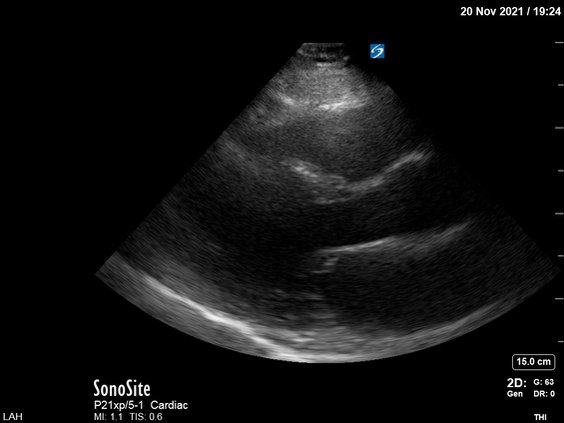

Pt emergently transferred to the ICU. POCUS was done. PLAX:

Obviously there was poor global LV systolic function but just to "play by the book", let's look at another view to confirm the first one. PSAX: